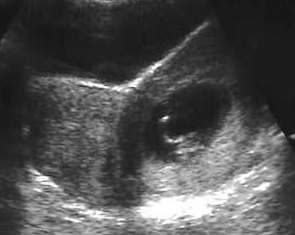

Utérus bicorne gravide. Signe du V vésical